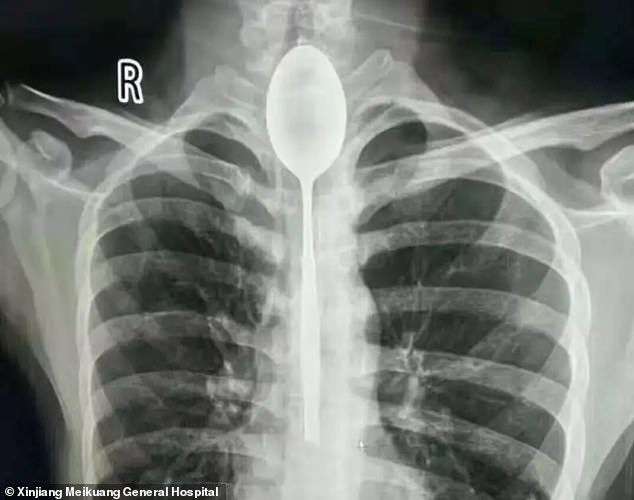

Depois de um jantar de amigos e uns copos a mais, começaram as irresponsabilidades. Tudo aconteceu na China, quando um homem engoliu uma colher de 20 cm depois de perder uma aposta. Porém, como não teve problemas respiratórios, bebia e…